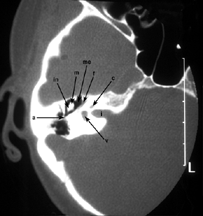

CT對頭頸部疾病的診斷也很有價值。例如,對眶內占位病變、鼻竇早期癌、中耳小膽指瘤、聽骨破壞與脫位、內耳骨迷路的輕微破壞、耳先天發育異常以及鼻咽癌的早期發現等。但明顯病變,X線平片已可確診者則無需CT檢查。

發病機制 臨床表現 診斷 檢查 治療正中。可觀察頭顱之大小、形狀及顱蓋骨,並可通過眼眶觀察岩骨及內聽道。2.側...、破裂孔、翼內外板和岩骨及中耳乳突均可清楚顯示。內聽道也經常顯示較好。鼻咽癌常有顱底骨破壞。內聽道片用來觀察後顱窩的情況,尤其是內聽道、岩椎、枕大...

原文摘錄 簡述彌衡 關於曹操 京劇概述 京劇劇本底、內聽道、視神經孔等特殊部位像,可顯示鞍背部位及後床突萎縮、蝶鞍輕微...。垂體瘤幾乎均有蝶鞍擴大,聽神經瘤大多有內聽道擴大等。2.腦血管造影:包括...,有些腫瘤如聽神經瘤和腦膜瘤平掃時密度對比不顯著或顯示為等密度病變,需增強...